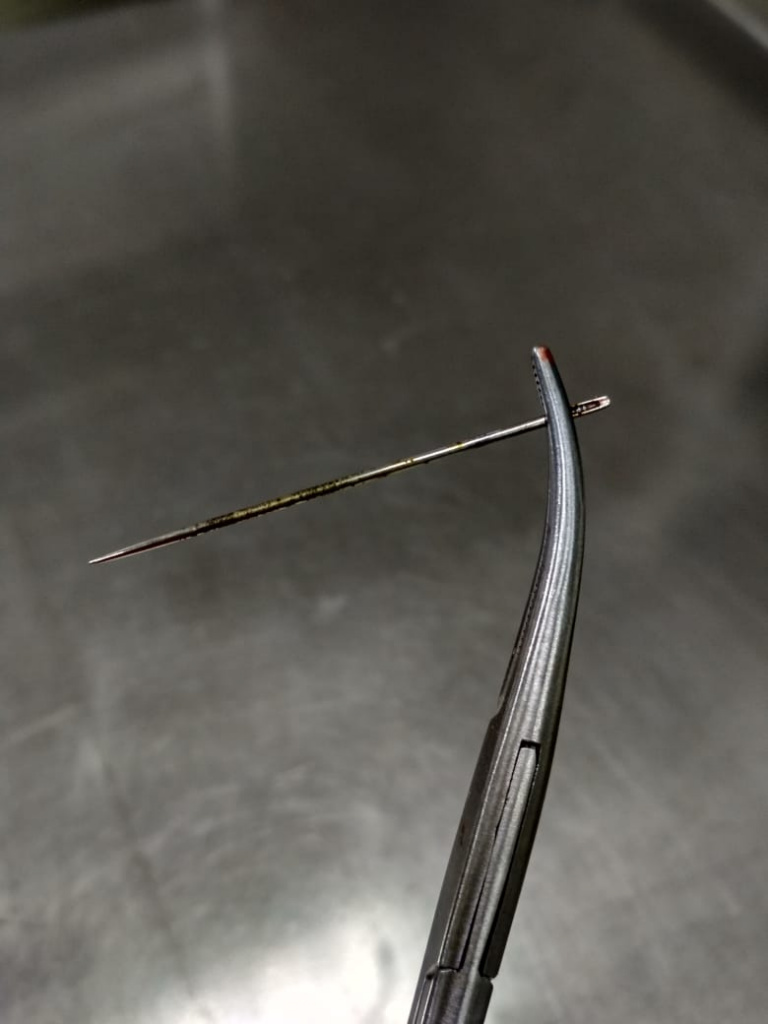

Инородное тело извлечено, проведена обработка ротовой полости антисептиком, назначена антибиотикотерапия.

Инородное тело извлечено, проведена обработка ротовой полости антисептиком, назначена антибиотикотерапия.